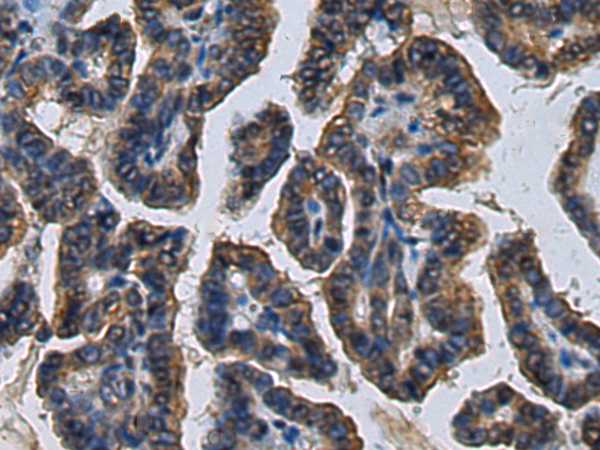

分类: 科研抗体货号: P02569别名: CPSF160; P/cl.18; HSU37012应用: IHC反应种属: Human, Mouse